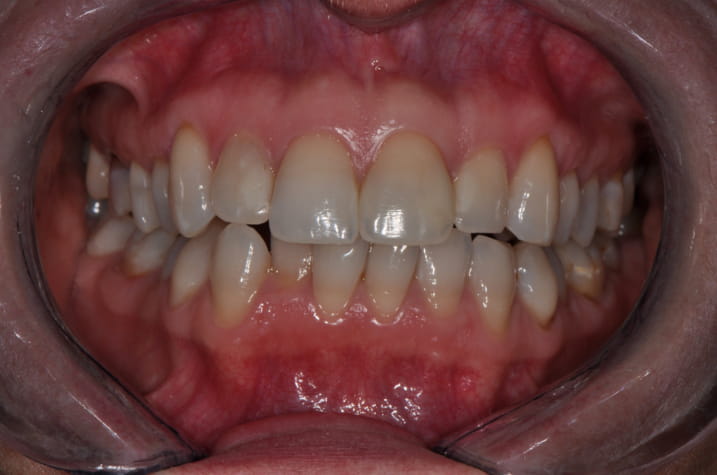

Wykonano zdjęcia uzębienia pacjentki (ryc. 2‑4). Przeprowadzono dokładne badanie mięśni żucia, zbadano ruchy żuchwy w trzech płaszczyznach – ruch otwierania jamy ustnej, ruch doprzedni oraz ruchy doboczne. Podczas otwierania zaobserwowano zbaczanie żuchwy w połowie ruchu, a następnie powrót do linii prostej. Bolesność mięśni żucia, stłoczenie zębów oraz nieprawidłowy tor ruchu żuchwy podczas otwierania nasuwał podejrzenie występowania problemów okluzyjnych.

Ryc. 3. Zdjęcie w pozycji maksymalnego zaguzkowania.